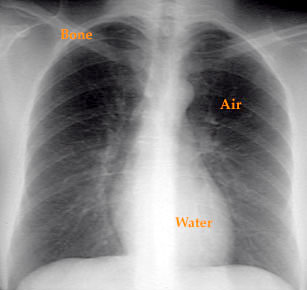

Densities in Chest X-Ray

Basically, you can recognize air, water and bone density on chest x-ray. Lung fields appear dark because of air. Ninety-nine percent of the lung is air. The pulmonary vasculature, interstitium constitute 1% and give the lacy lung pattern. Heart, vessels, liver and diaphragm are liquid density. Vertebrae, sternum and ribs obviously cast a bone density.